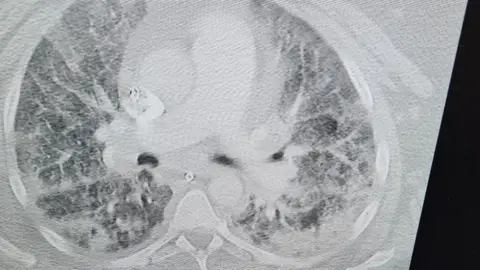

Just as we came home and were trying to get our life on track, they confirmed I had lung disease and it's never going to get any better.

With the lung disease, I have to have lung function tests and I am due to have breathing tests. I will be constantly on medication and I also have a thyroid problem since having Covid.